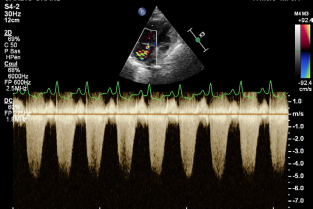

Le thème de la cardiologie sera abordé cette année. Le Groupe d’étude en cardiologie a répondu présent à notre invitation et a élaboré un programme orienté vers la pratique au quotidien.

- établir une démarche diagnostique lors de toux, de dyspnée, de syncope ou lors de fatigabilité ;

- orienter les examens complémentaires lors d’un souffle cardiaque ;

- classifier et diagnostiquer une cardiopathie féline ;

- traiter une cardiomyopathie à phénotype hypertrophique ;

- explorer et décrire les principes de traitement des stades précliniques de la MVD ;

- décrire les principes de prise en charge d'un OAP ;